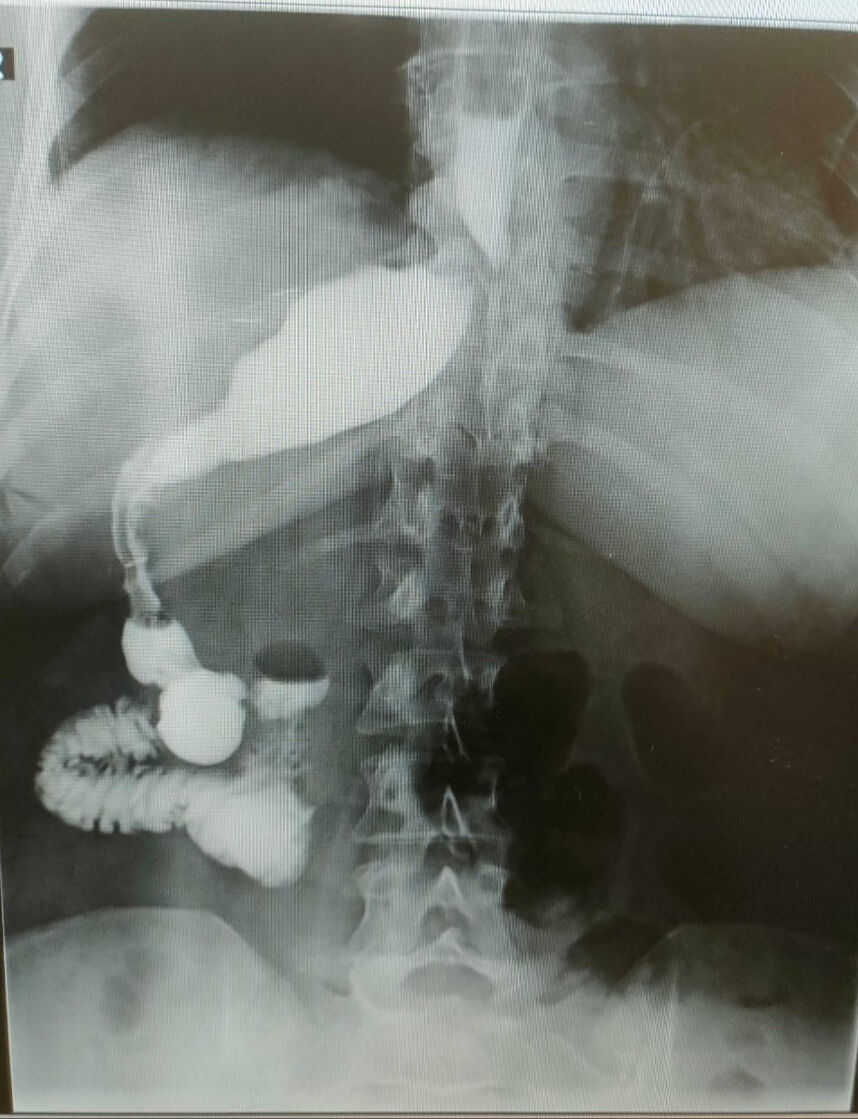

Ameliyat esnasında cerrahi ekip, Kirscht'in midesini karaciğerinin arkasında, sağ tarafta buldu. Bu sıra dışı anatomik durum, hem hasta hem de ekibin şaşkınlık yaşamasına neden oldu.

Ameliyatı gerçekleştiren Memorial Antalya Hastanesi Genel Cerrahi Bölüm Başkanı Prof. Dr. Alihan Gürkan, yaşadıkları şaşkınlığı şu sözlerle dile getirdi: “Çok yapılan bu operasyonlar içerisinde hastanın değişik bir anomalisi vardı.

100 binde bir görüldüğü söyleniyor. Organların hepsi ters olabiliyor. Bu daha sık görülen bir şey ama bu hastada bütün organlar yerli yerinde ama sadece mide sağ tarafa kaymış. Yani karaciğerin arkasına gitmiş. Operasyona başladığımızda mideyi bulamadık. Karaciğeri kaldırınca mideyi sağ tarafta gördük.

Bu çok nadir bir durum. 2023 yılı verilerine göre, böyle bir tüp mide ameliyatı dünyada yalnızca 50 kişiye uygulanmış. Biz de bu vakayı başarıyla gerçekleştirdik. Teknik açıdan bizi zorlayan ancak deneyimimizi artıran bir ameliyat oldu”

"OPERASYONUN AYNA GÖRÜNTÜSÜNÜ YAPTIK"

Prof. Dr. Gürkan, ameliyatın detaylarına değinerek, “Tüp mide operasyonunun ayna görüntüsünü yaptık. Normalde sol tarafta yaptığımız obezite ameliyatını bu hastada sağ tarafta gerçekleştirdik. Midenin karaciğerin arkasında olması ameliyat süresini 15 dakika uzattı ve toplamda 1 saat sürdü. Bizim için de hoş bir tesadüf oldu” diye konuştu.